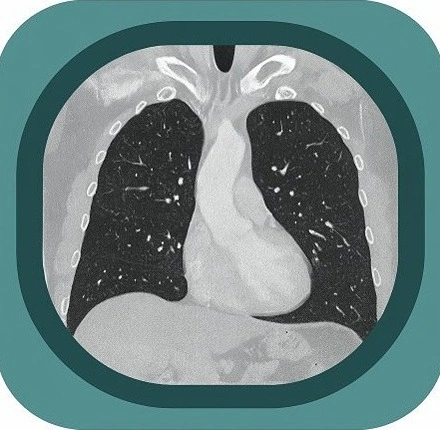

Explore full-body CT anatomy in 3 planes. Our high-resolution, carefully labelled images reveal micro-anatomy—ideal for radiologists, radiographers and surgeons.